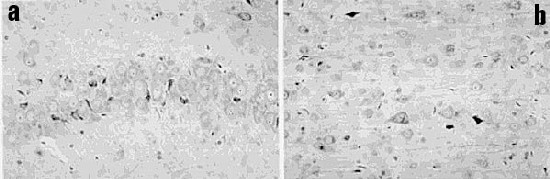

Fig. 1 :

a) Coupe agrandie des parties centrales du cerveau d'un rat non exposé (témoin), colorée pour l'albumine qui apparaît en brunâtre dans les parties centrales inférieures du cerveau, l'hypothalamus : ceci est normal. Dans le coin inférieur gauche (flèche) une tache brune représente une fuite occasionnelle.

b) Parties centrales du cerveau d'un rat exposé aux fréquences radio, coloré pour l'albumine. Les multiples foyers brunâtres représentent les fuites de plusieurs vaisseaux sanguins.

Les animaux témoins ont montré soit aucune, soit une certaine positivité donnant souvent lieu à des interrogations, quant à l'albumine en dehors de l'hypothalamus (Figure 1 a). Chez un animal, un nombre modéré de neurones sombres ont été observés alors que chez tous les autres animaux, de telles modifications n'étaient pas présentes.

Les animaux exposés ont habituellement montré beaucoup de foyers positifs à l'albumine dans les substances blanche et grise autour des vaisseaux sanguins les plus ténus (Figure 1 b).